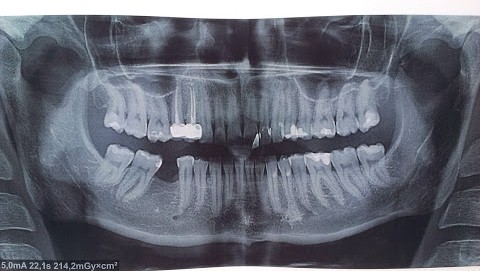

6 лет назад была удалена шестёрка. До сих пор не лечили. Сейчас, перед имплантацией, начали ортодонтическое лечение. Врач настаивает на удалении всех восьмёрок. Я этого не хочу (они меня не беспокоят) и не могу поверить, что их сохранение может воспрепятствовать удачному ортодонтическому лечению (скученности никакой не наблюдаю).

Естественно прав врач, хотите Вы или нет. Тем более, что Ваше мнение не имеет медицинского объяснения. Три восьмерки необходимо удалить абсолютно точно (18, 28, 38). Я думаю, что объяснять Вам не стоит причину удаления, так как ортодонт скорее всего Вам все рассказал.